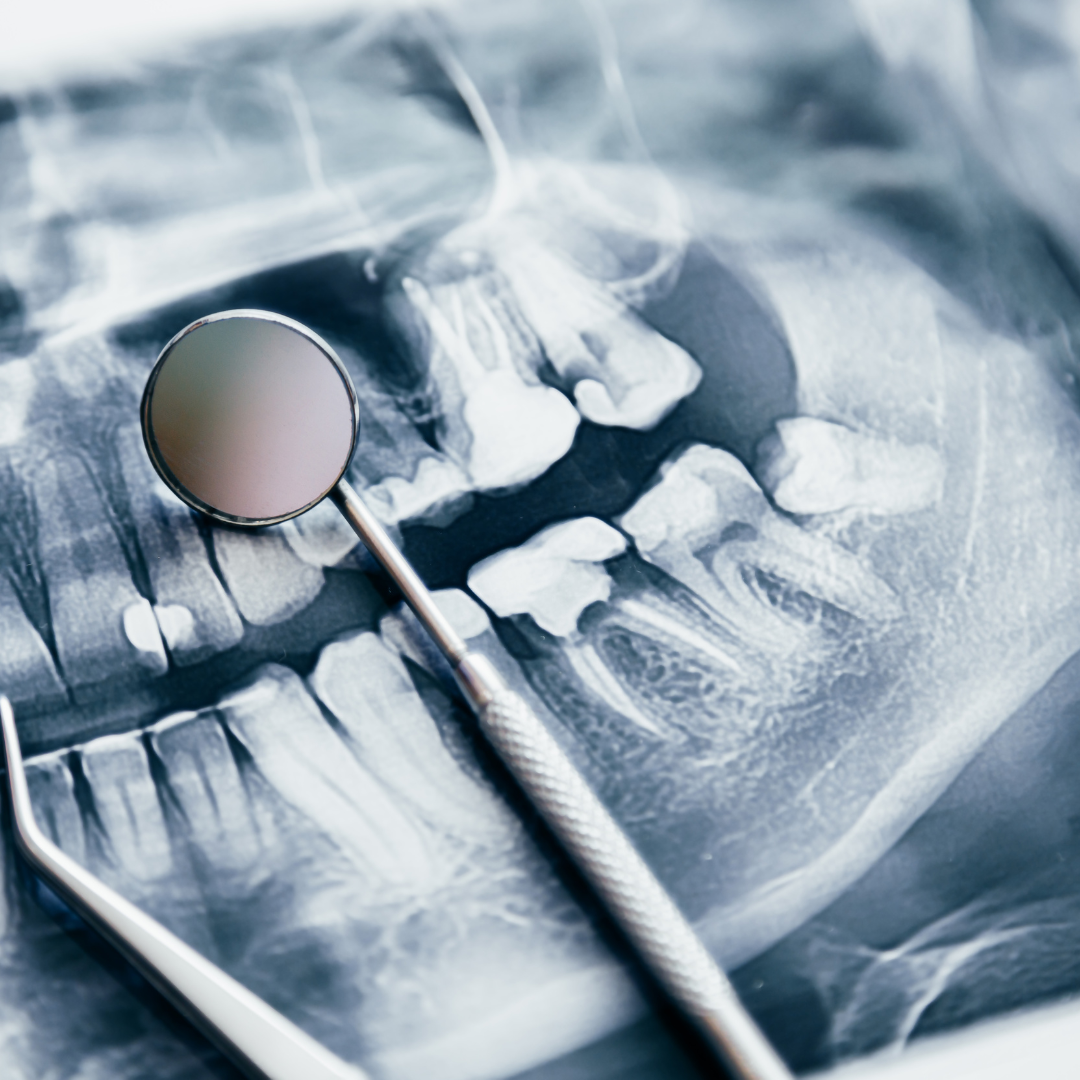

Digital X-rays

X-rays are essential in dentistry to detect problems not visible to the naked eye. Digital X-rays, an advancement over traditional methods, use less radiation and provide immediate.